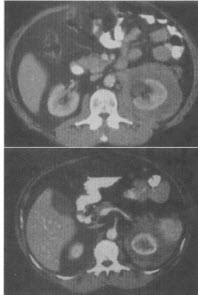

- 单项选择题 男,65岁,全身浅表淋巴结肿大,根据所示图像,最可能的诊断是()。

- C